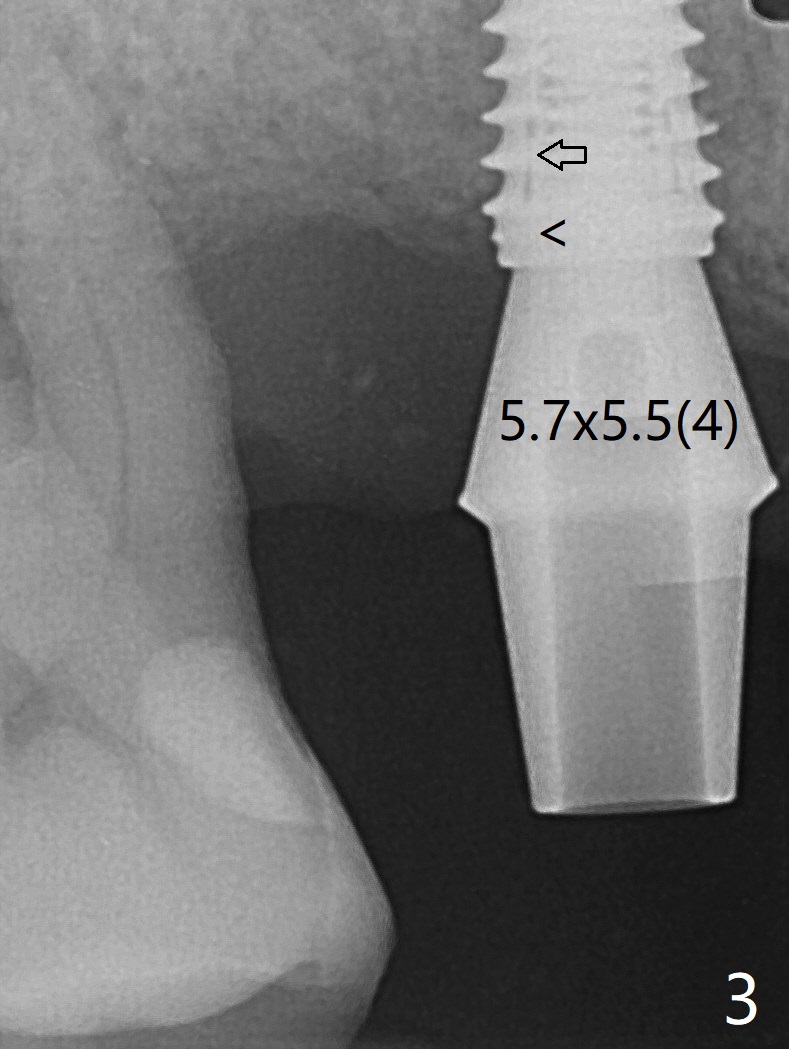

使用来自钻头的自体骨做提升,植体植入后,颊侧骨板薄,刚好骨下。使用5.5毫米profile drill后,放置愈合基台,术后三个月脱落,他再次要求修复,甚至提出退款,不愿意回诊所,因为他有糖尿病,新冠病毒高危人群。 放置小号愈合基台(图二)。他原来托牙是Valplast,没有occlusal rests,不能经过修改临时使用,可能将直接放置修复基台做临时牙冠。放置修复基台后(图三(术后三个月)),制作临时牙冠时,发现前者有些松动,后者就没有粘固。当基台完全就位,它最冠方与植体没有间隙(箭头),根方有间隙(空心箭头)。其实愈合基台也是一样(图一,二)。后来植体松动(术后4个月),拔除,植骨(图四),颊侧骨板缺失(图五:B)。植骨后5个月2号牙疼痛需要拔除种植(图七),与3号牙一起种植(图六),颊侧骨板修复,但是高度有所下降(箭头)。The narrow ridge with the intact buccal plate (Fig.8 >) can hold a 4x8.5 mm implant. The buccal plate is lost 4 months postop (Fig.9) and restores 5 months post graft (Fig.10). Return to Upper Molar Immediate Implant, No Deviation Coronal and Apical Gap in IBS implant Protect Graft Xin Wei, DDS, PhD, MS 1st edition 06/22/2020, last revision 05/02/2021